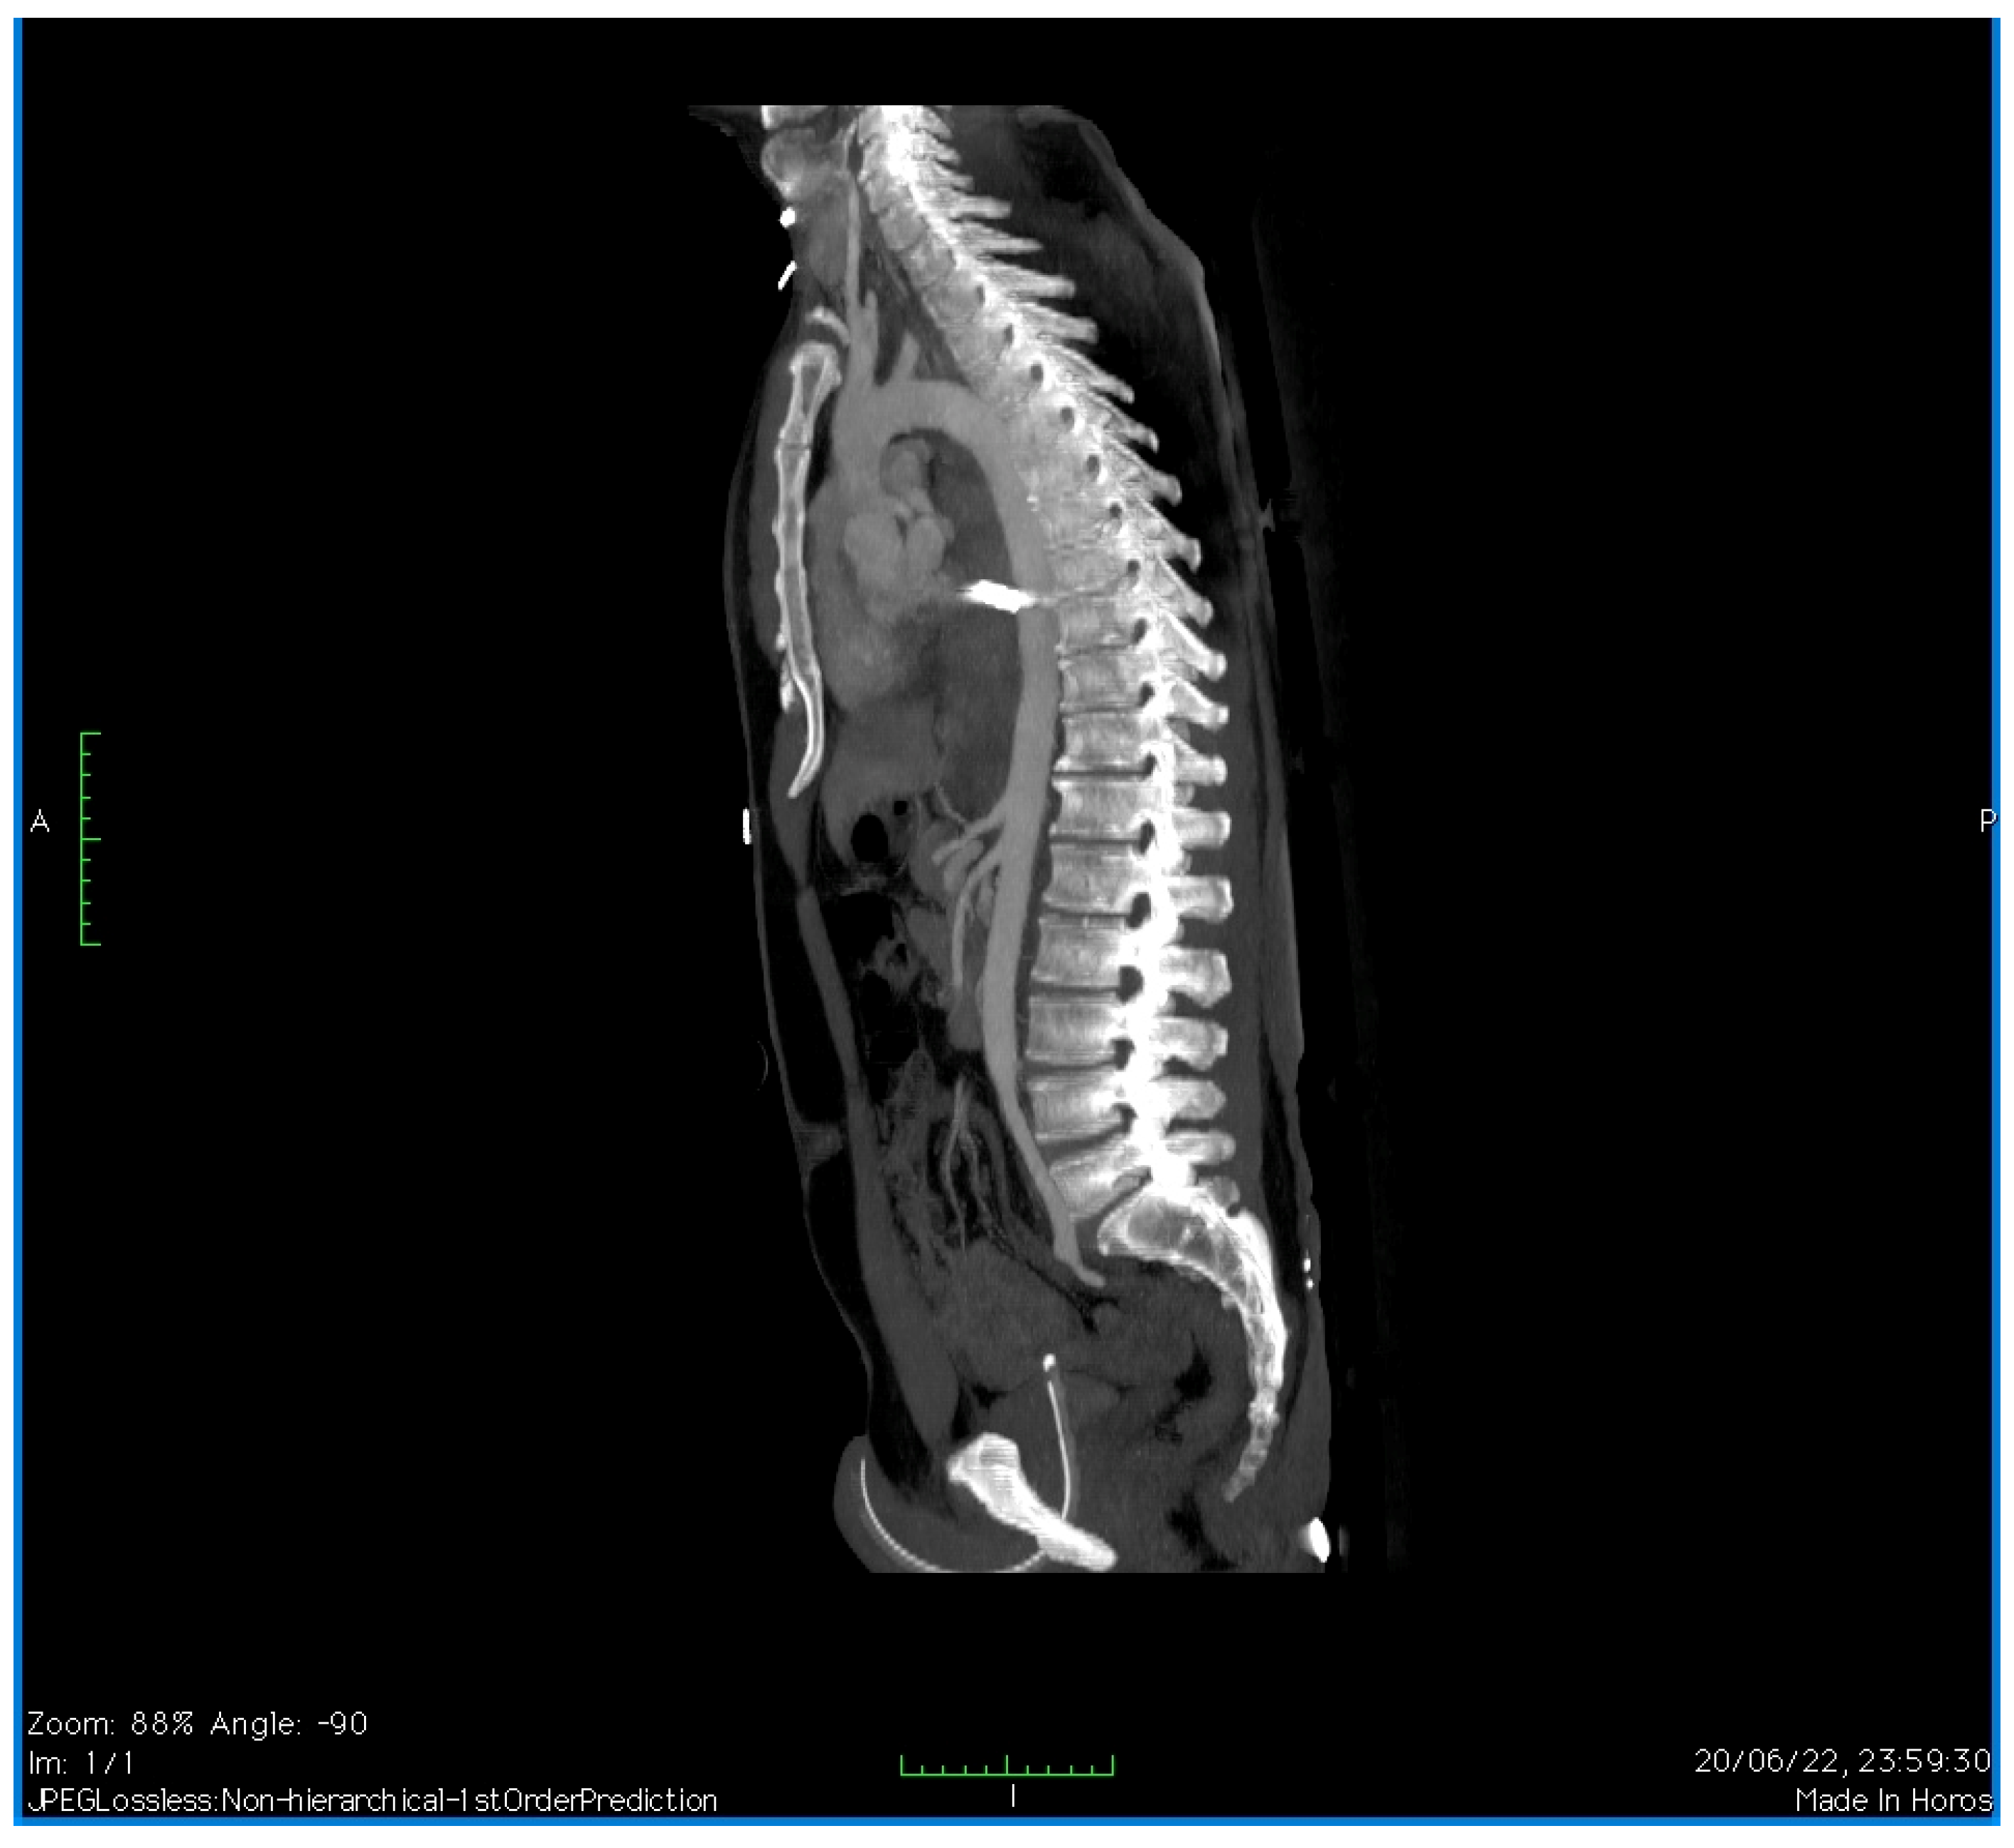

2. Case Presentation